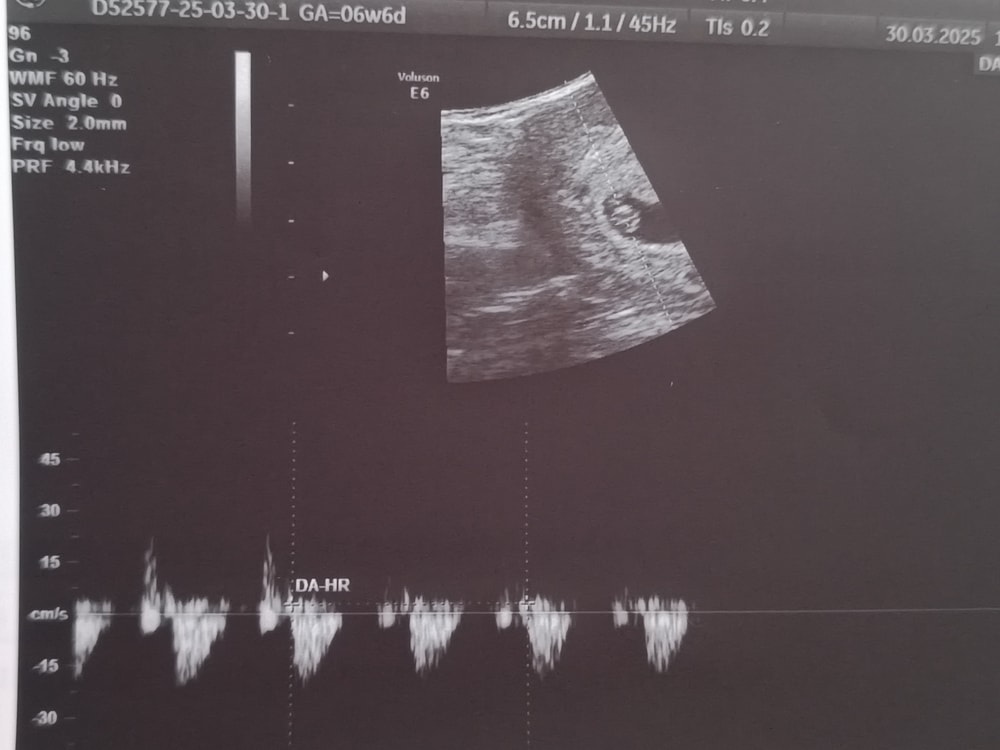

Первое УЗИ